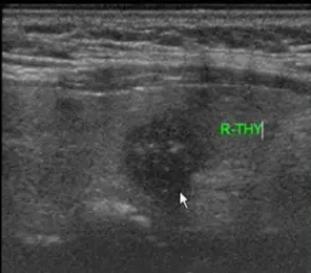

到院后先为李女士安排了 甲功八项和四维弹性成像 检查,检查结果发现结节后方回声衰减,其内可见微钙化灶。